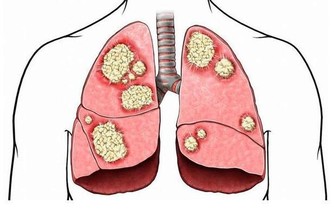

一旦反復出現這些症狀,不但會導致整體的免疫功能受到影響,還會影響到心臟的正常供血,患有心梗或者是冠心病等一系列心血管疾病的概率會比較高。所以在進入夏季時,一定要做好心臟的養護工作。那麼,在夏季時到底該如何養護心臟呢?

總而言之,進入夏季之後一定要注意做好心臟的養護工作,除了以上5點以外,每天還應該適當補充水分,但注意應該以白開水為主,也可以適當飲用一些金花茶、菊花茶等,都有著降火氣以及養護心臟健康的作用。

如果在夏季時出現了心悸、心慌、胸悶、胸痛、呼吸不暢、頭暈等現象,必須快速入院檢查並治療,才能最大程度維護心臟健康。